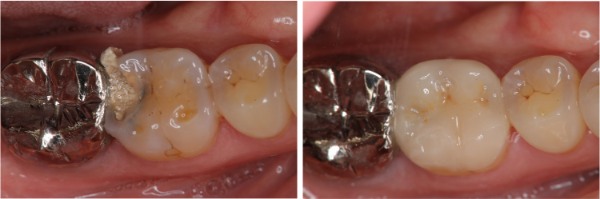

陶瓷冠塊體

貼面邊緣完整

無殘膠存在

術前、術後比較